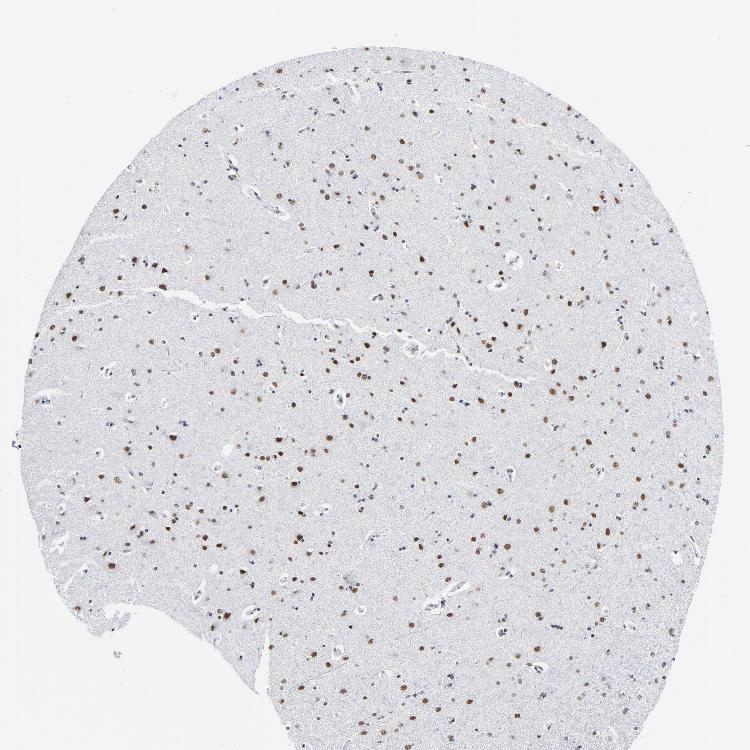

CEREBRAL CORTEX - Antibody stainingi

Antibody staining in the annotated cell types in the current human tissue is reported as not detected, low, medium, or high, based on conventional immunohistochemistry profiling in selected tissues. This score is based on the combination of the staining intensity and fraction of stained cells.

Each image is clickable and will lead to virtual microscopy that enables deeper exploration of all samples and also displays staining intensity scores, fraction scores and subcellular localization as well as patient and tissue information for each sample.

Antibody HPA000427Antibody CAB004680

Endothelial cells MediumNot detected

Glial cells Not detectedMedium

Neuronal cells HighMedium

Neuropil Not detectedNot detected